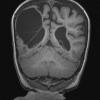

Hypoxia-Ischemia, fetal-neonatal

Porencephaly (4)